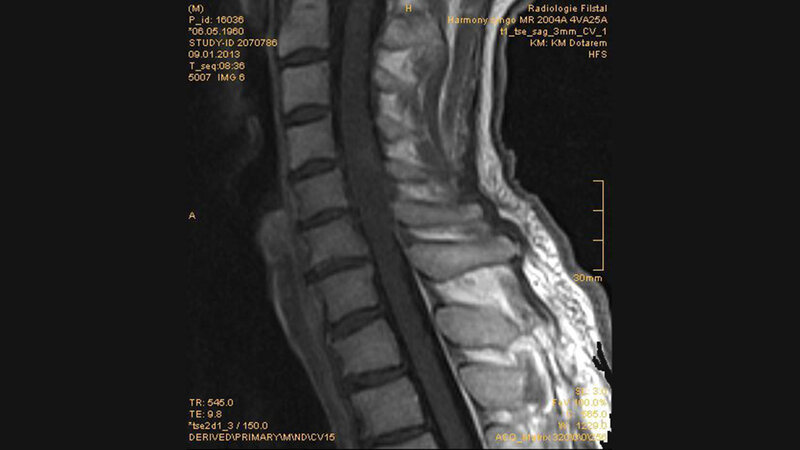

Tumoröse Veränderungen: medulläres Gangliogliom

Der dieses Mal vorgestellte Fall behandelt einen seltenen Tumor, der vorrangig intrazerebral mit temporaler Dominanz, gelegentlich auch im Bereich der Neuroachse vorkommen kann: das Gangliogliom.

Das Gangliogliom kann in jedem Bereich des Zentralnervensystems vorkommen. Gangliogliome des Rückenmarks sind sehr selten. Der Tumor ist sehr gut zu operieren, die adjuvante Therapie ist kontrovers.